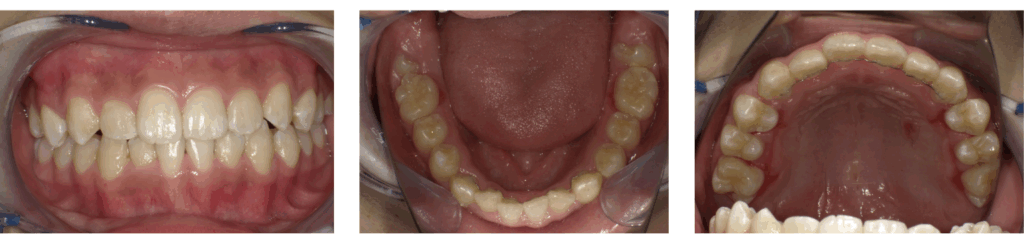

症例2:急速拡大装置のみ使用した症例

| 年齢 | 11歳 |

| 性別 | 男子 |

| 治療の理由(主訴) | ガタガタの見た目を治したい。 目立つのでワイヤー装置は付けたくない。 |

| 治療方法 | 顎顔面矯正 |

| 治療期間 | 1年4か月 |

| 費用 | 44万円 |

治療前

装置装着

拡大完了

治療後